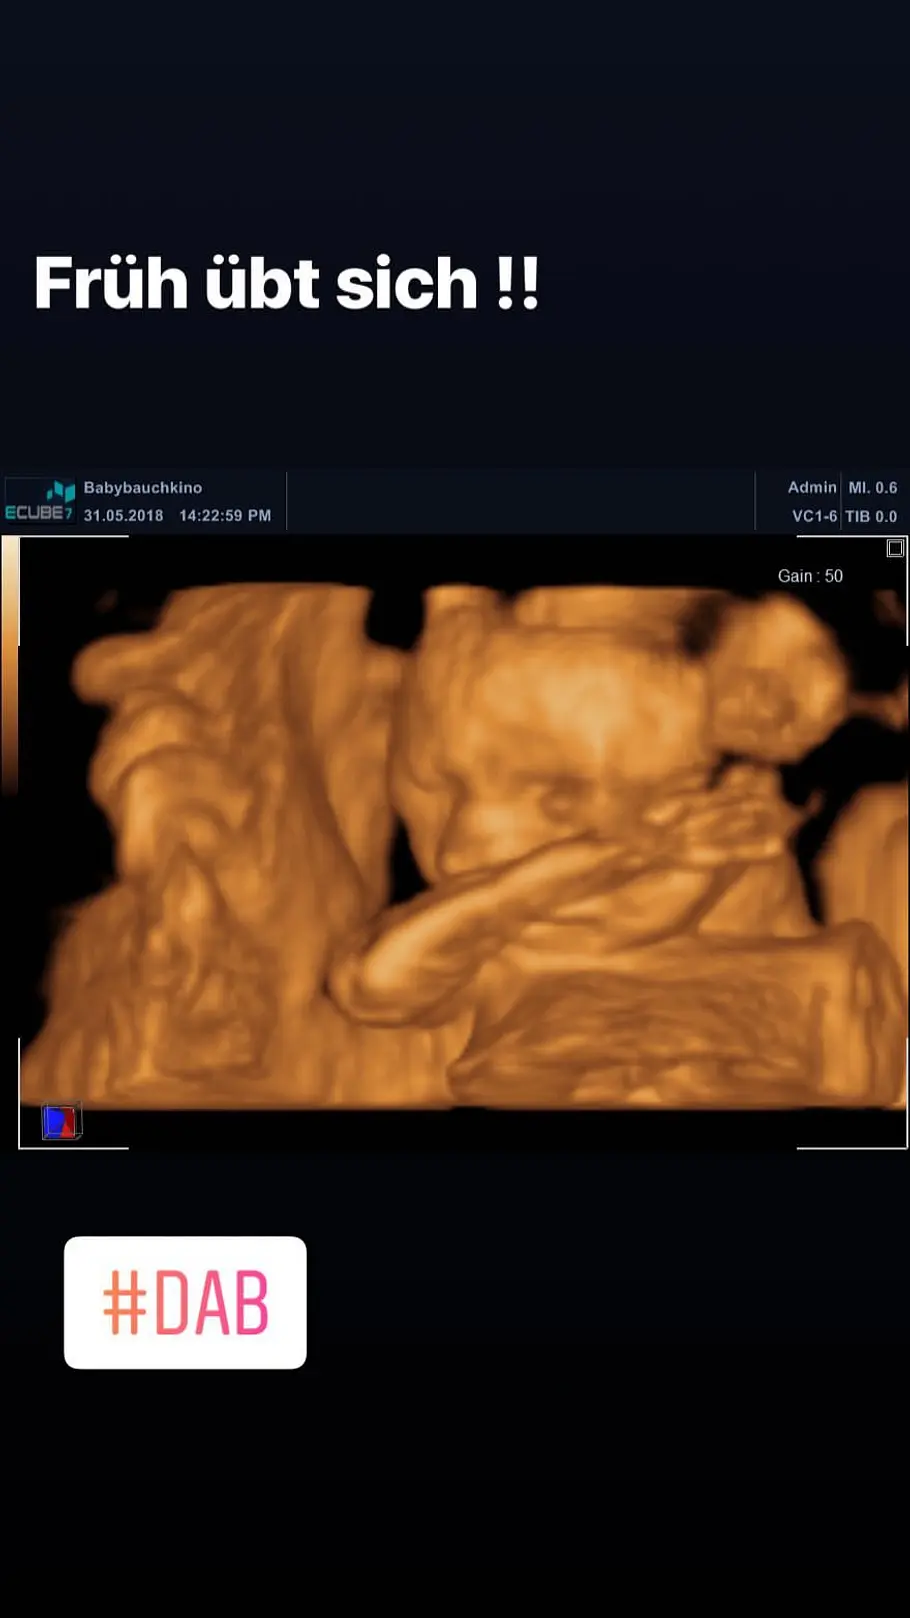

Denise ohne Pascal beim Ultraschall-Termin

Zum gestrigen Ultraschall-Termin beim Frauenarzt begleitete nicht Pascal seine Denise, sondern ihre beste Freundin. Dabei zählen diese Termine doch für werdende Eltern zu den wichtigsten Momenten während der ganzen Schwangerschaft! Und auch dass der BTN-Darsteller alle gemeinsamen Bilder von sich und Denise von seinem Instagram-Profil gelöscht hat, ist kein gutes Zeichen, was die Ehe der beiden anbelangt. Stattdessen hält er seine Abonnenten mit regelmäßigen Party-Posts mit seinen Jungs auf dem Laufenden.